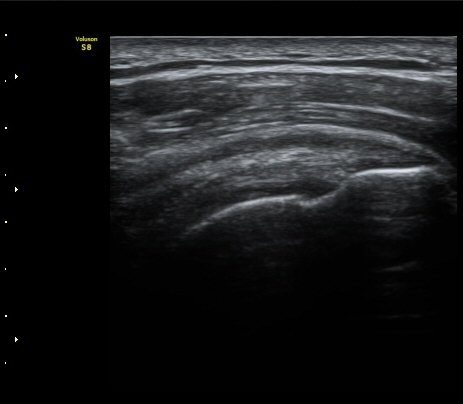

À̵ιڱ٠Ⱦ´Ü¸é°Ë»ç¿¡¼­ Á¤¸Æ³¶ÀÇ ºÎÁ¾ÀÌ °üÂûµÊ(±×¸² 1).